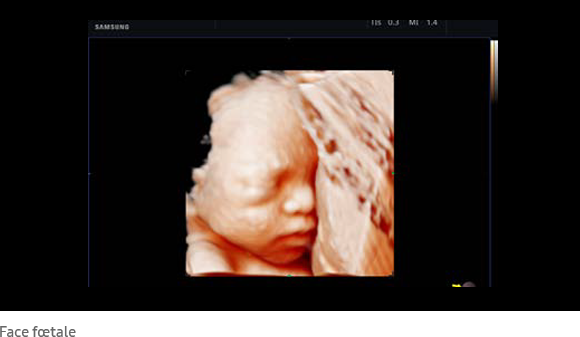

Le RealisticVue™ propose des rendus anatomiques de haute résolution en 3D/4D. Une source lumineuse est modélisée afin de permettre un effet d'ombre sur les structures et de surligner les zones d'intérêt.